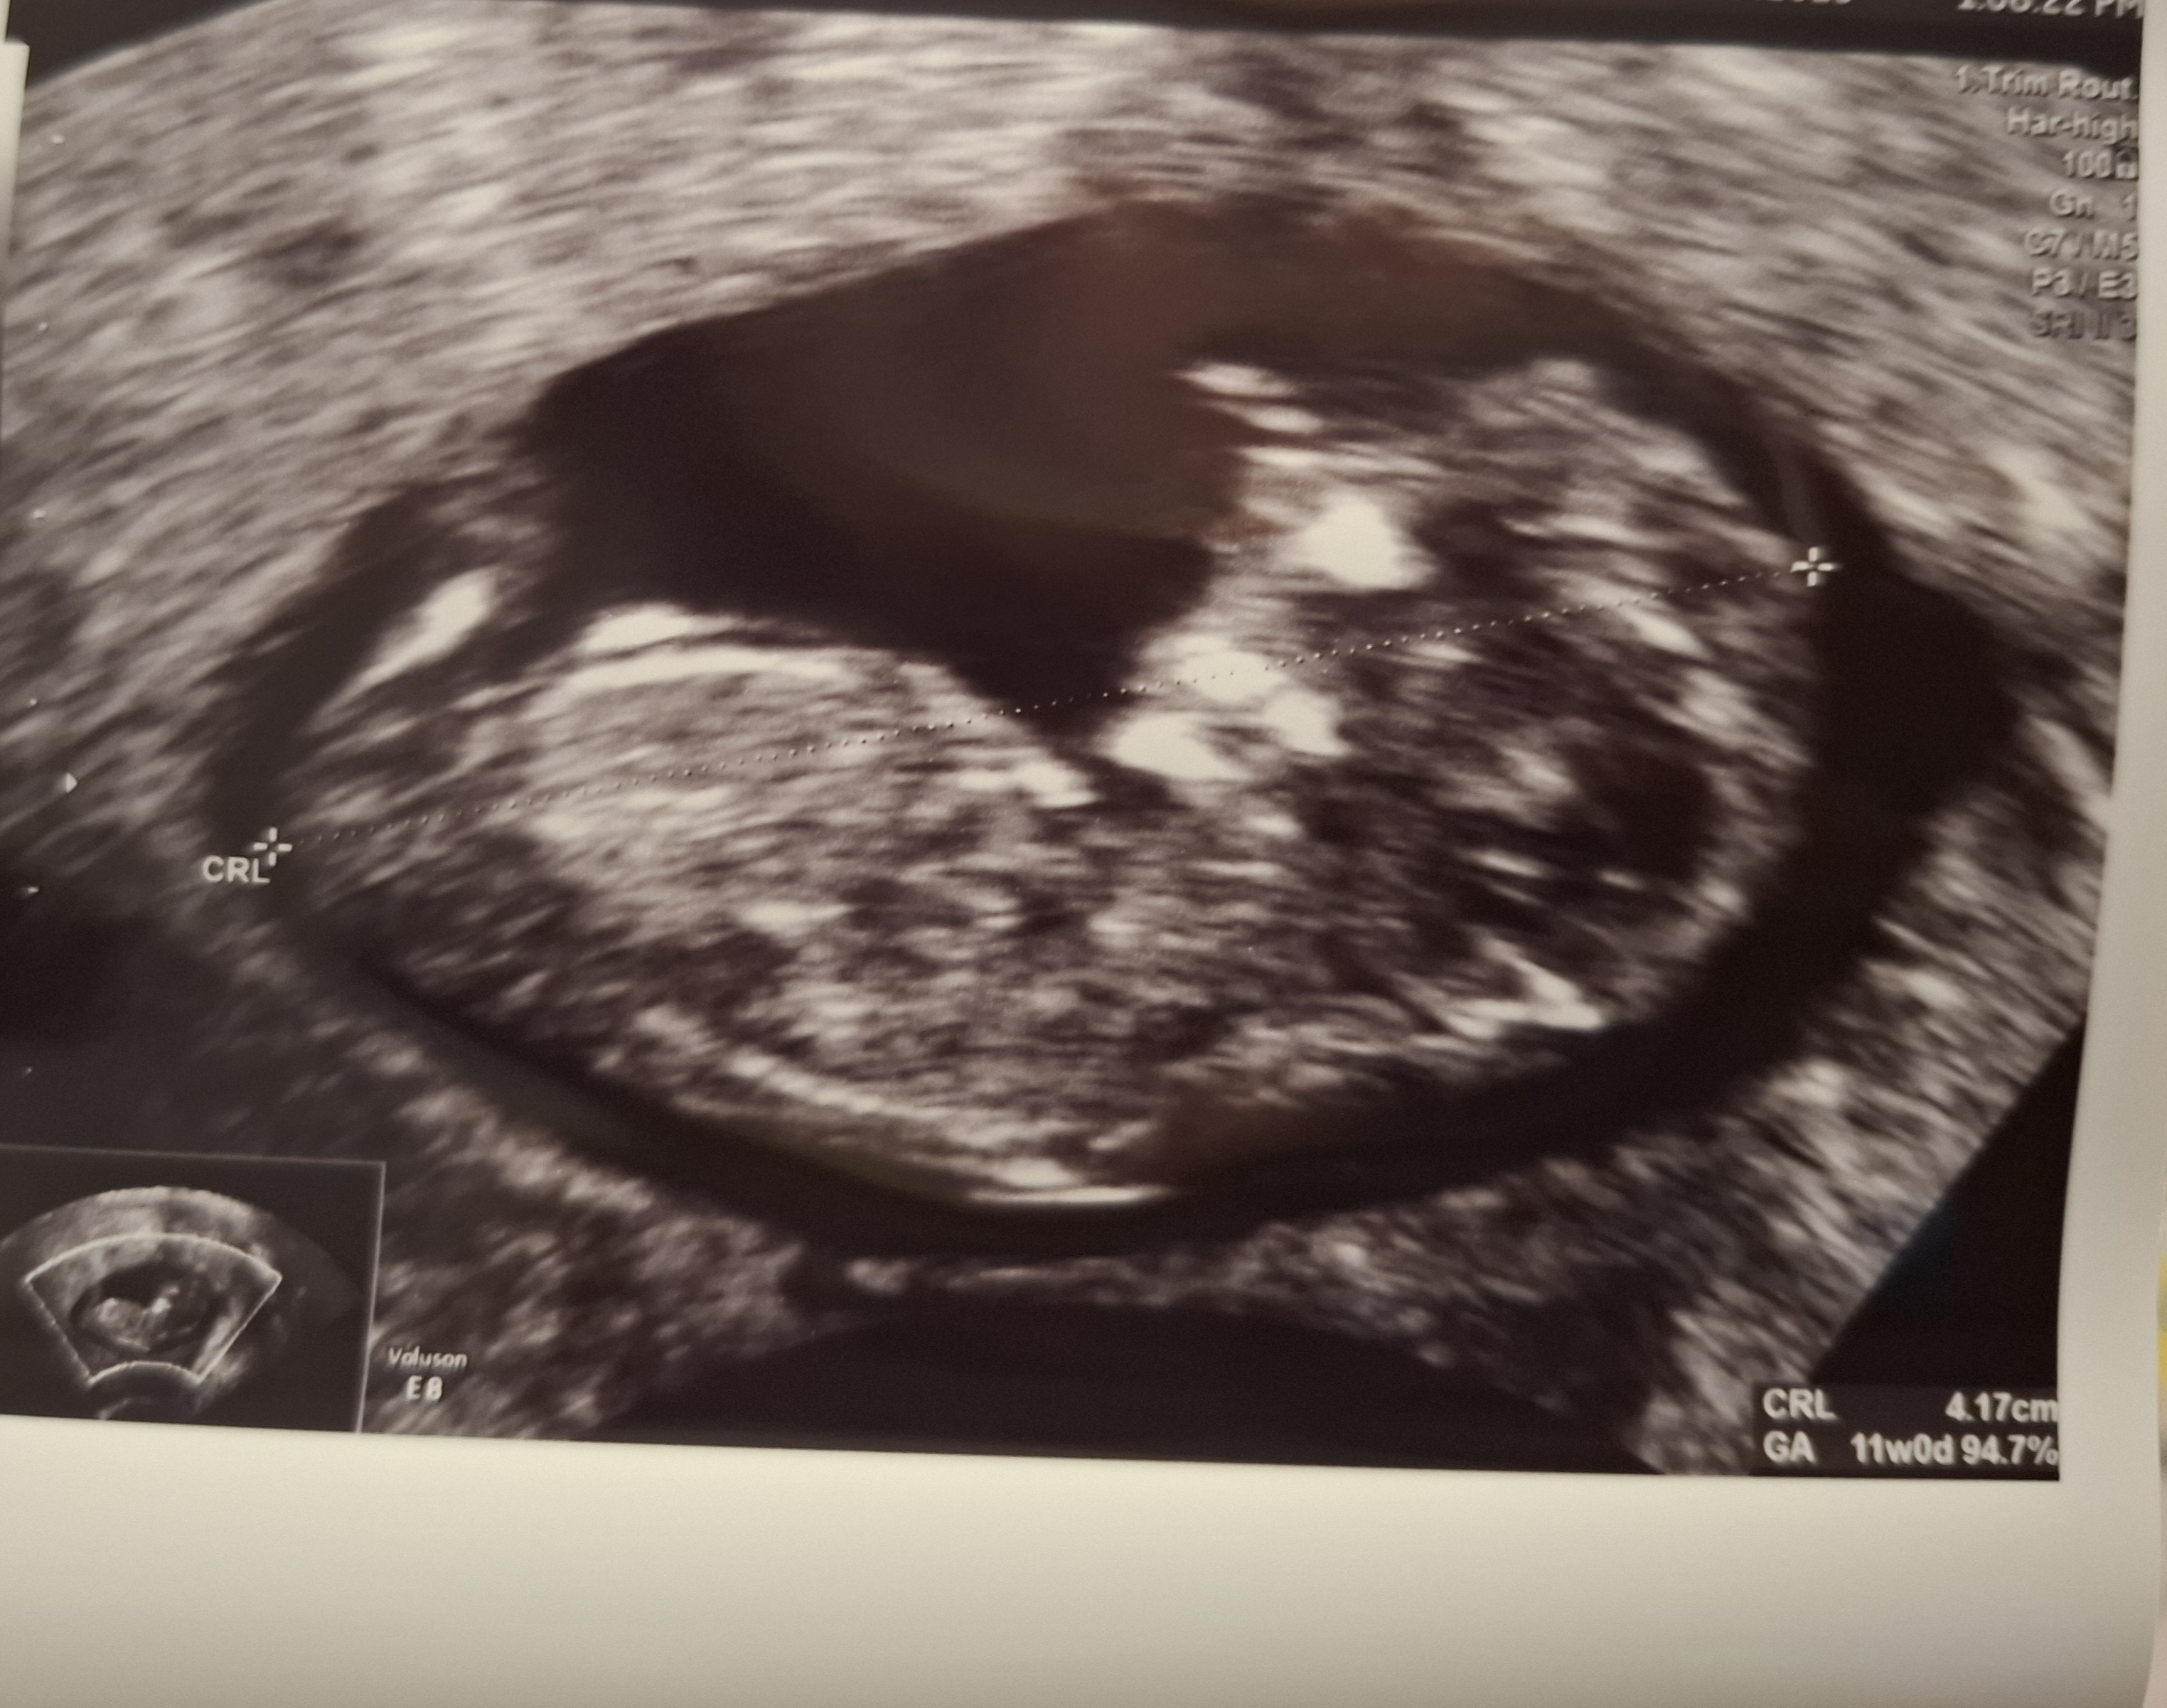

To mamy 2 dni różnicy i w terminie i w prenatalnychTermin mam na 17.02 a dzis umowilam sie na prenatalne 7.08![]()